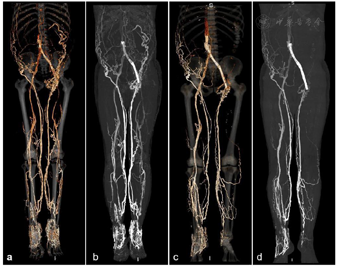

双下肢静脉CTV像示左侧髂外静脉-髂总静脉-下腔静脉支架留置影,左侧髂外静脉远端可见少许对比剂充盈,余支架管腔内可见低密度充盈缺损影,左侧髂外静脉、髂总静脉未见对比剂充盈;左侧腹股沟可见多发侧支血管显影,左侧腹壁内侧-左肾静脉侧支血管建立影像(图1,图2),右侧髂外静脉、髂总静脉及下腔静脉可见对比剂充盈,密度不均匀;双足、双下肢皮下多发迂曲静脉显影,双侧大隐静脉充盈良好,左侧股静脉近端充盈缺损,血管纤细,密度不均(图1)。诊断:左侧髂外静脉-髂总静脉-下腔静脉支架留置,支架内血栓形成,左侧腹股沟区、左侧腹壁内测-左肾静脉及腹壁静脉建立。介入治疗后复查双下肢静脉CTV,可见左侧大隐静脉开口以近支架内血管大致通畅,支架以远端下肢静脉未见明确显影,左侧腹股沟区侧支循环较前减少,左侧腹壁内侧-左肾静脉侧支血管较前减轻(图3、图4)。

下肢静脉栓塞的诊断金标准为DSA检查[1],但DSA是有创检查,准备时间长,耗费人力物力,同时DSA存在过量辐射暴露风险且检查费用较高,检查过程中易损伤血管壁导致新鲜血栓形成[2,3,4]。对比DSA,CT血管检查操作简便,显影效果好,安全微创,对比剂用量少,成像范围大,辐射剂量低。根据对比研究,可以准确评估下肢静脉的通畅性,能展现整个下肢静脉系统情况及静脉栓塞疗效评估,与DSA吻合度高。双源CT低kV高mAs球管技术,在降低患者辐射剂量前提下,增强了碘对比剂衰减,在CT血管检查中用低流速低对比剂用量亦可获得高质量的CT血管诊断图像。本例双下肢CTV采用90kV,双筒双流速度2.5ml/s直接注入下肢静脉各100ml混合剂(造影剂10%+盐水90%),可获得可观的静脉血管图像(图1)。对比常规CT(120kV),低kV技术大幅度降低辐射剂量。此外,CT血管后处理灵活方便,结合探针分析,更是可以细节、清晰地观察支架内外管腔及管壁情况(图2、图3),为临床诊断提供准确的影像学资料,为患者病变及时发现及进一步治疗提供可靠依据[5]。CT作为微创检查方式,"三低"双下肢CTV可常规应用,替代传统120kV,满足临床诊断需求同时提高患者的舒适度,降低辐射剂量,减少并发症,并适合血栓患者术前明确诊断及术后疗效评估(图4)。为了实现常规低kV血管成像,其他先进的技术也被使用,如CARE Dose4D(实时自动曝光控制)和ADMIRE(高级模型迭代重建)。在本病例中,有效剂量仅为0.65mSv。